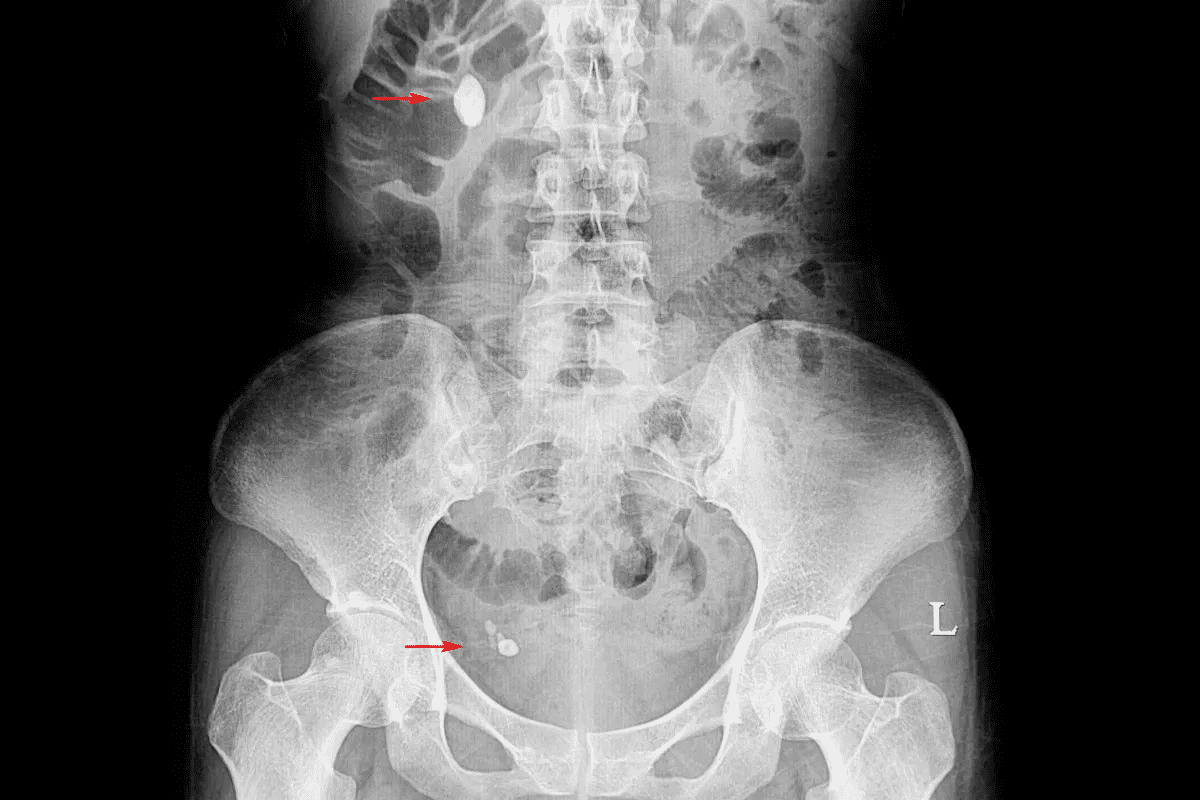

Imaging Tests for Kidney Stones

Imaging tests are key in finding kidney stones. The main tests are:

- Ultrasound: A non-invasive test that uses sound waves to create images of the kidneys, helping to identify stones and possible blockages.

- Computed Tomography (CT) Scan: Gives detailed images of the kidneys, ureters, and bladder. It helps doctors find stones and other issues precisely.

- X-ray: Can spot certain types of kidney stones, mainly those that show up on X-rays.

These tests help doctors know the size, location, and number of stones. This info is key for planning treatment.